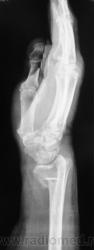

Фрагменты с увеличением.

Если срок сращения 4 недели, то признаки консолидации выражены соответственно сроку достаточно хорошо. Перелом компрессионный, поэтому произошел вывих в л/л суставе. Можно или нет его было устранить в амбулаторных условиях - судить не берусь. Осколок кортикала в луче "захряснет", может, рассосется - ничего страшного.

неприятная ситуация(особенно если не было первичной репозиции) есть оппределенные правила ведения таких переломов, первичный снимок, сразу после репозиции, через 4-5 дней после репозиции и если нет вторичного смещения в гипсе то через 4-5 недель уже без гипса. ситуация на данный момент спорная, лучше наложить аппарат Илизарова для дальнейшей иммобилизации и профилактики контрактуры л\зап сустава. если возраст пациентки почтенный, то гипсовая иммобилизация доолжна быть продлена до 8 недель.